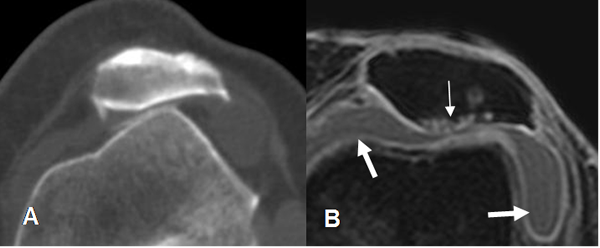

Fig 58. Luxación crónica de patela.

A: TAC axial. Lateralización de la patela, con pérdida del espacio patelofemoral y formación de osteofitos.

B: RM axial en FFE T1 STIR. Lateralización de la patela, con pérdida del cartílago articular y lesiones osteocondrales en el vértice. Existe derrame articular asociado. (Flechas gruesas).